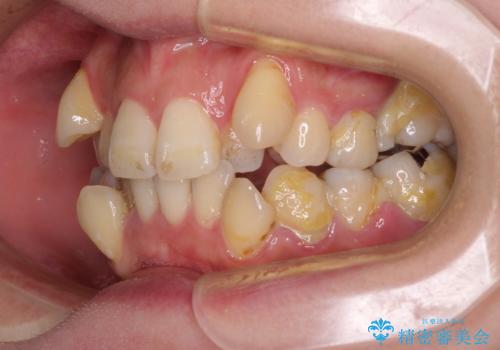

- 上下前歯のデコボコを気にして来院された患者様です。

デコボコが強いため、非抜歯で矯正をすると出っ歯仕上がりとなるため、上下左右の第一小臼歯4本を抜歯することとしました。